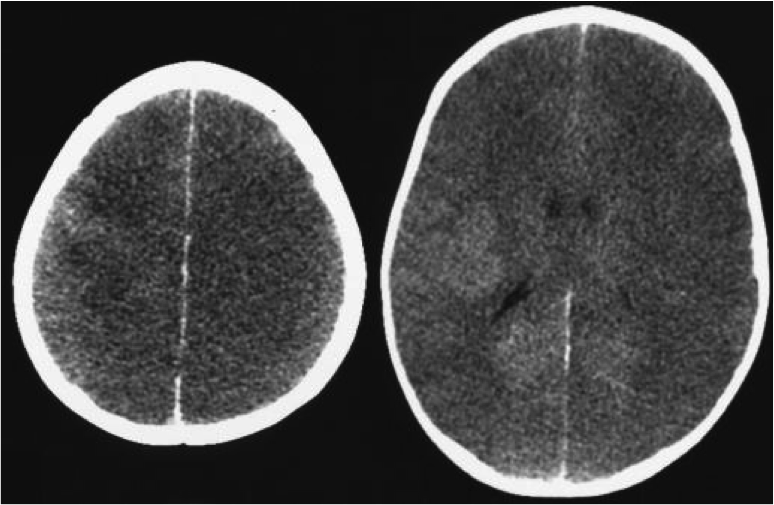

WHat do you see?

Diffuse cerebral edema